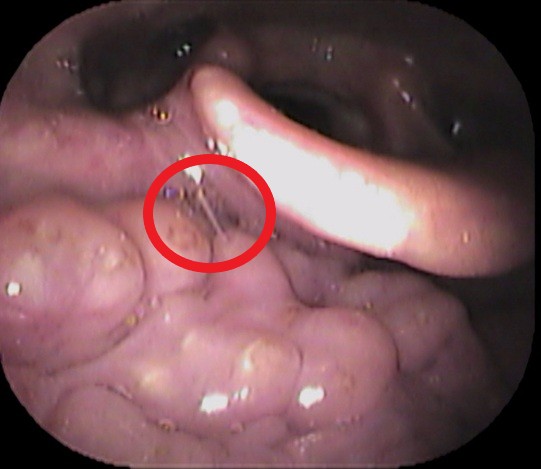

声帯の一部に白い隆起がありました。

どれかと言いますと↓

赤丸部分です。

逆流性食道炎のアンケート結果が高値で、逆流性食道炎が原因の喉頭肉芽腫と診断しました。

喉頭肉芽腫とは、慢性的な刺激が原因で声帯の後方の粘膜が炎症を起こし、白く隆起する疾患です。

逆流性食道炎が原因で声帯後方の粘膜が白く隆起したと考えられます。

逆流性食道炎の治療薬で、白い隆起は縮小していきました。

「喉違和感」「詰まった感じ」がある方は、耳鼻咽喉科の受診をおススメいたします